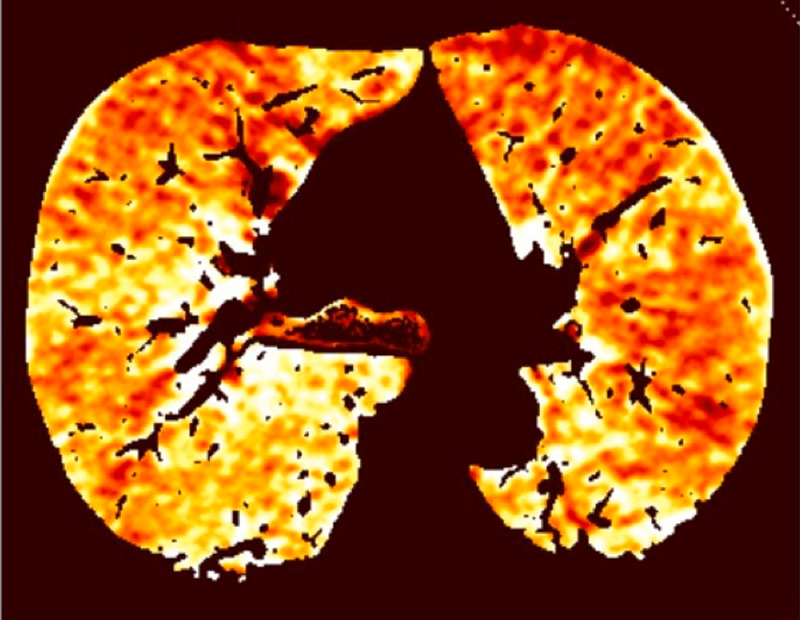

Because of the attenuation properties of iodine at two different photon energies (80 and 140 kV), a dual-energy technique can generate pulmonary blood volume maps and quantify the iodine concentration in the parenchyma. It has been demonstrated that the local distribution of iodine contrast medium correlates well with pulmonary perfusion [18]. The generated pulmonary blood volume maps are combined with mediastinal images to permit simultaneous analysis of the grey-scale vasculature and colour-scale parenchymal perfusion, with parenchymal images (fig. 1). Furthermore, the iodine concentration in the lung allows an objective and quantitative analysis.

Figure 1

Technical principles. The dual-energy system with two X-ray tubes permits simultaneous 80 (A) and 140 kV (B) image acquisition in order to generate an iodine map (C) fused with mediastinal reconstructions (D).